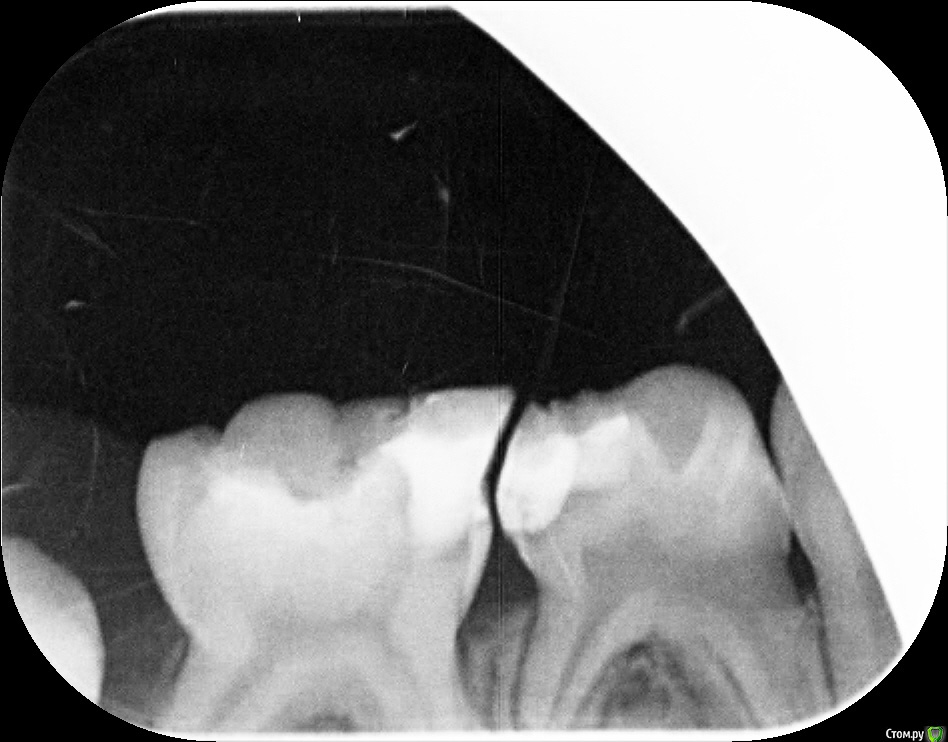

Zenden Опубликовано 2 ноября, 2019 Поделиться Опубликовано 2 ноября, 2019 (изменено) Добрый день, ребенку 5.5 лет, жалуется на зубную боль нижнего 4 или скорее 5 зуба справа, но не можем понять точно какой именно зуб болит, и почему он вообще разболелся если на обоих зубах уже есть пломбы.В клинике, где делали снимки, врач предположила про 5-ку, предложила убрать пломбу и пролечивать каналы. Хочется услышать еще мнений что делать, спасибо. если это важно, то перед зубной болью ребенок перенес ОРВИ Изменено 2 ноября, 2019 пользователем Zenden Ссылка на комментарий